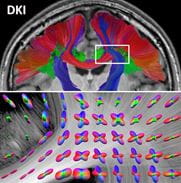

Fiber tractography using diffusional kurtosis imaging

Diffusional kurtosis imaging (DKI) is well-suited to tractography because, unlike diffusion tensor imaging, it can resolve fiber crossings (bottom panel).

However, in almost 30percent of voxels in an MRI image, two or more fiber tracts cross, causing the typical algorithms used with DTI to fail. As a result, DTI cannot determine the direction of both fibers and can mistakenly interpret the crossing as an abnormality or lesion. Such fiber crossings can be resolved effectively with the far more sensitive DSI method but at the cost of longer imaging times and more complicated post-processing.

DKI, which collects more information than DTI but less than DSI, offers a useful compromise. Like DSI, it can resolve fiber crossings and so accurately map the trajectories of white matter fiber tracts. Like DTI, it can do so in a clinically relevant time frame. The connectomes of disease that will be developed by the Human Connectome Project could offer useful reference maps against which to compare tractography obtained from at-risk patients, leading to earlier and more definitive diagnoses of neurological diseases. However, that promise will only be realized if there is a reliable clinical tool for performing fiber tractography. Both sensitive and clinically translatable, DKI is certainly a strong contender to be that tool.